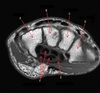

What is letter A?

SUBSCAPULARIS MUSCLE

What is letter B?

HEAD OF HUMERUS

What is letter C?

INFRASPINATUS MUSCLE

What is letter D?

GLENOID